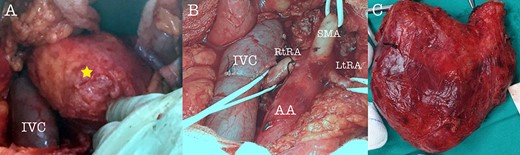

A 43-year-old Caucasian male with an unremarkable past medical history was referred for a retroperitoneal tumor diagnosed on a computerized tomography (CT) scan performed for progressively worsening lower back pain. Physical examination was unremarkable and the laboratory values including tumor markers were within normal range. The abdominal CT scan demonstrated a large solid non-enhancing retroperitoneal mass, with a well-defined margin, measuring 9.6 cm × 9.3 cm, located anteriorly to the aorta and displacing the inferior vena cava (IVC), pancreas, the superior mesenteric artery (SMA) and the renal vessels (Fig. 1). Patient underwent an exploratory laparotomy and a tumor was found lying in the retroperitoneum adherent to aorta, IVC, SMA, pancreas and renal vessels (Fig. 2). Complete right medial visceral rotation was performed and the small bowel mesentery was mobilized exposing the retroperitoneum. Meticulous dissection of the tumor from the aorta IVC and their main abdominal branches was performed and the specimen was excised. The specimen consisted of a well-circumscribed, solid tan to yellow tumor measuring ~9 × 9 cm encased by a fibrous capsule. Histological, no atypia or mitotic activity was evident and the tumor was composed of variably sized mature ganglion cells with satellite cells deposited in a neuromatous stroma. All three lymph nodes included within the surgical specimen were not infiltrated. The ganglion cells stained positive for S-100 protein, glial fibrillary acidic protein and neuron-specific enolase (NSE) while Ki-67 labeling index was <1% (Fig. 3). The final pathology report was RGN. Postoperative course was uncomplicated. Patient is well on a 2-years follow-up without clinical or radiographic evidence of recurrent disease.

Intraoperative view of the tumor (A), after tumor resection (B) and tumor specimen (C), (AA: abdominal aorta, RtRA: right renal artery, LtRA: left renal artery, IVC: inferior vena cava).